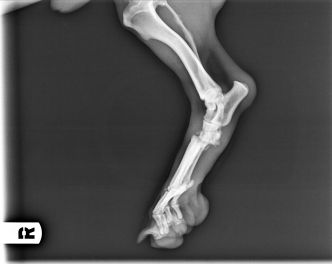

Enseguida nos hicimos cargo de él. Tras pasar una primera revisión veterinaria, decidimos trasladarlo a Madrid a una casa de acogida para tener una segunda opinión de un traumatólogo de nuestra confianza. El resultado fue el diagnóstico de luxación de codo en la pata delantera, y de fractura de huesos con luxación en la pata trasera. El problema es que estas lesiones tenían una antigüedad de unas 5 semanas, por lo que ya se había empezado a formar fibrosis y callo. Con todo ello se decidió dejar que la fractura siguiese su consolidación, y operar la luxación de codo, para intentar que recuperase completamente su funcionalidad.

Como se puede ver en las radiografías, con dos cirugías sobre la articulación, se consiguió la perfecta recolocación.